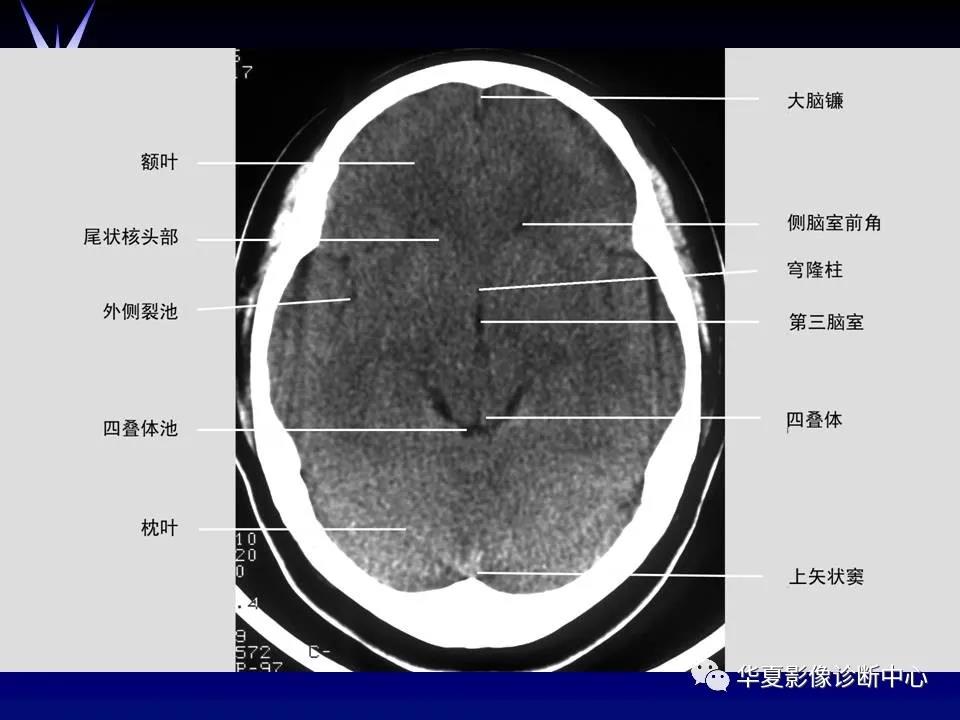

来源:华夏影像诊断中心